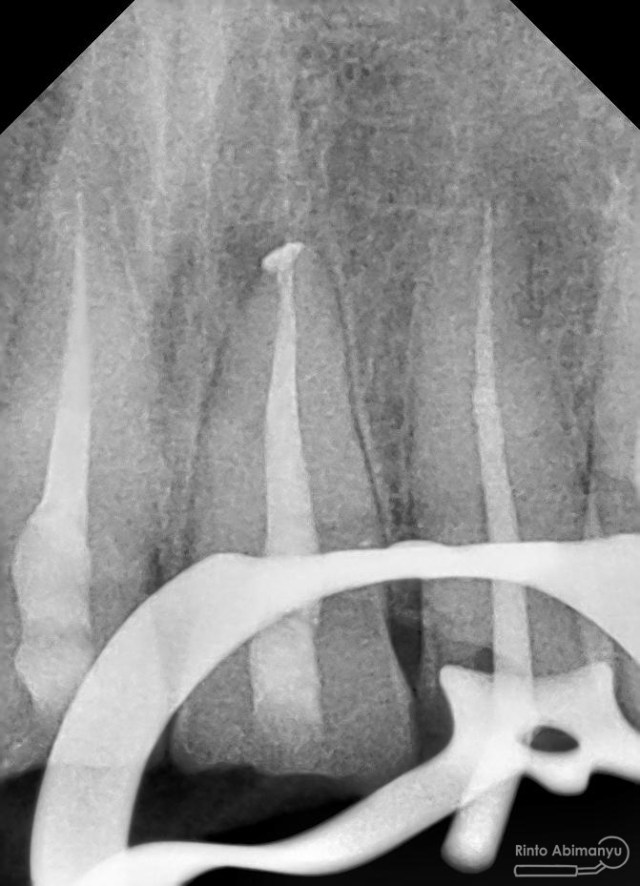

Foto radiografis trial guttap gigi 22

Nah dari foto ronsen ini juga saya melakukan evaluasi hasil pengisian pada gigi 11 21 nya… alhamdulillah pengisian yang kemarin terlihat sepanjang kerja dan padat serta rapat… Pada gigi 22 nya pun pengepasan guttap terlihat sudah sepanjang kerja…